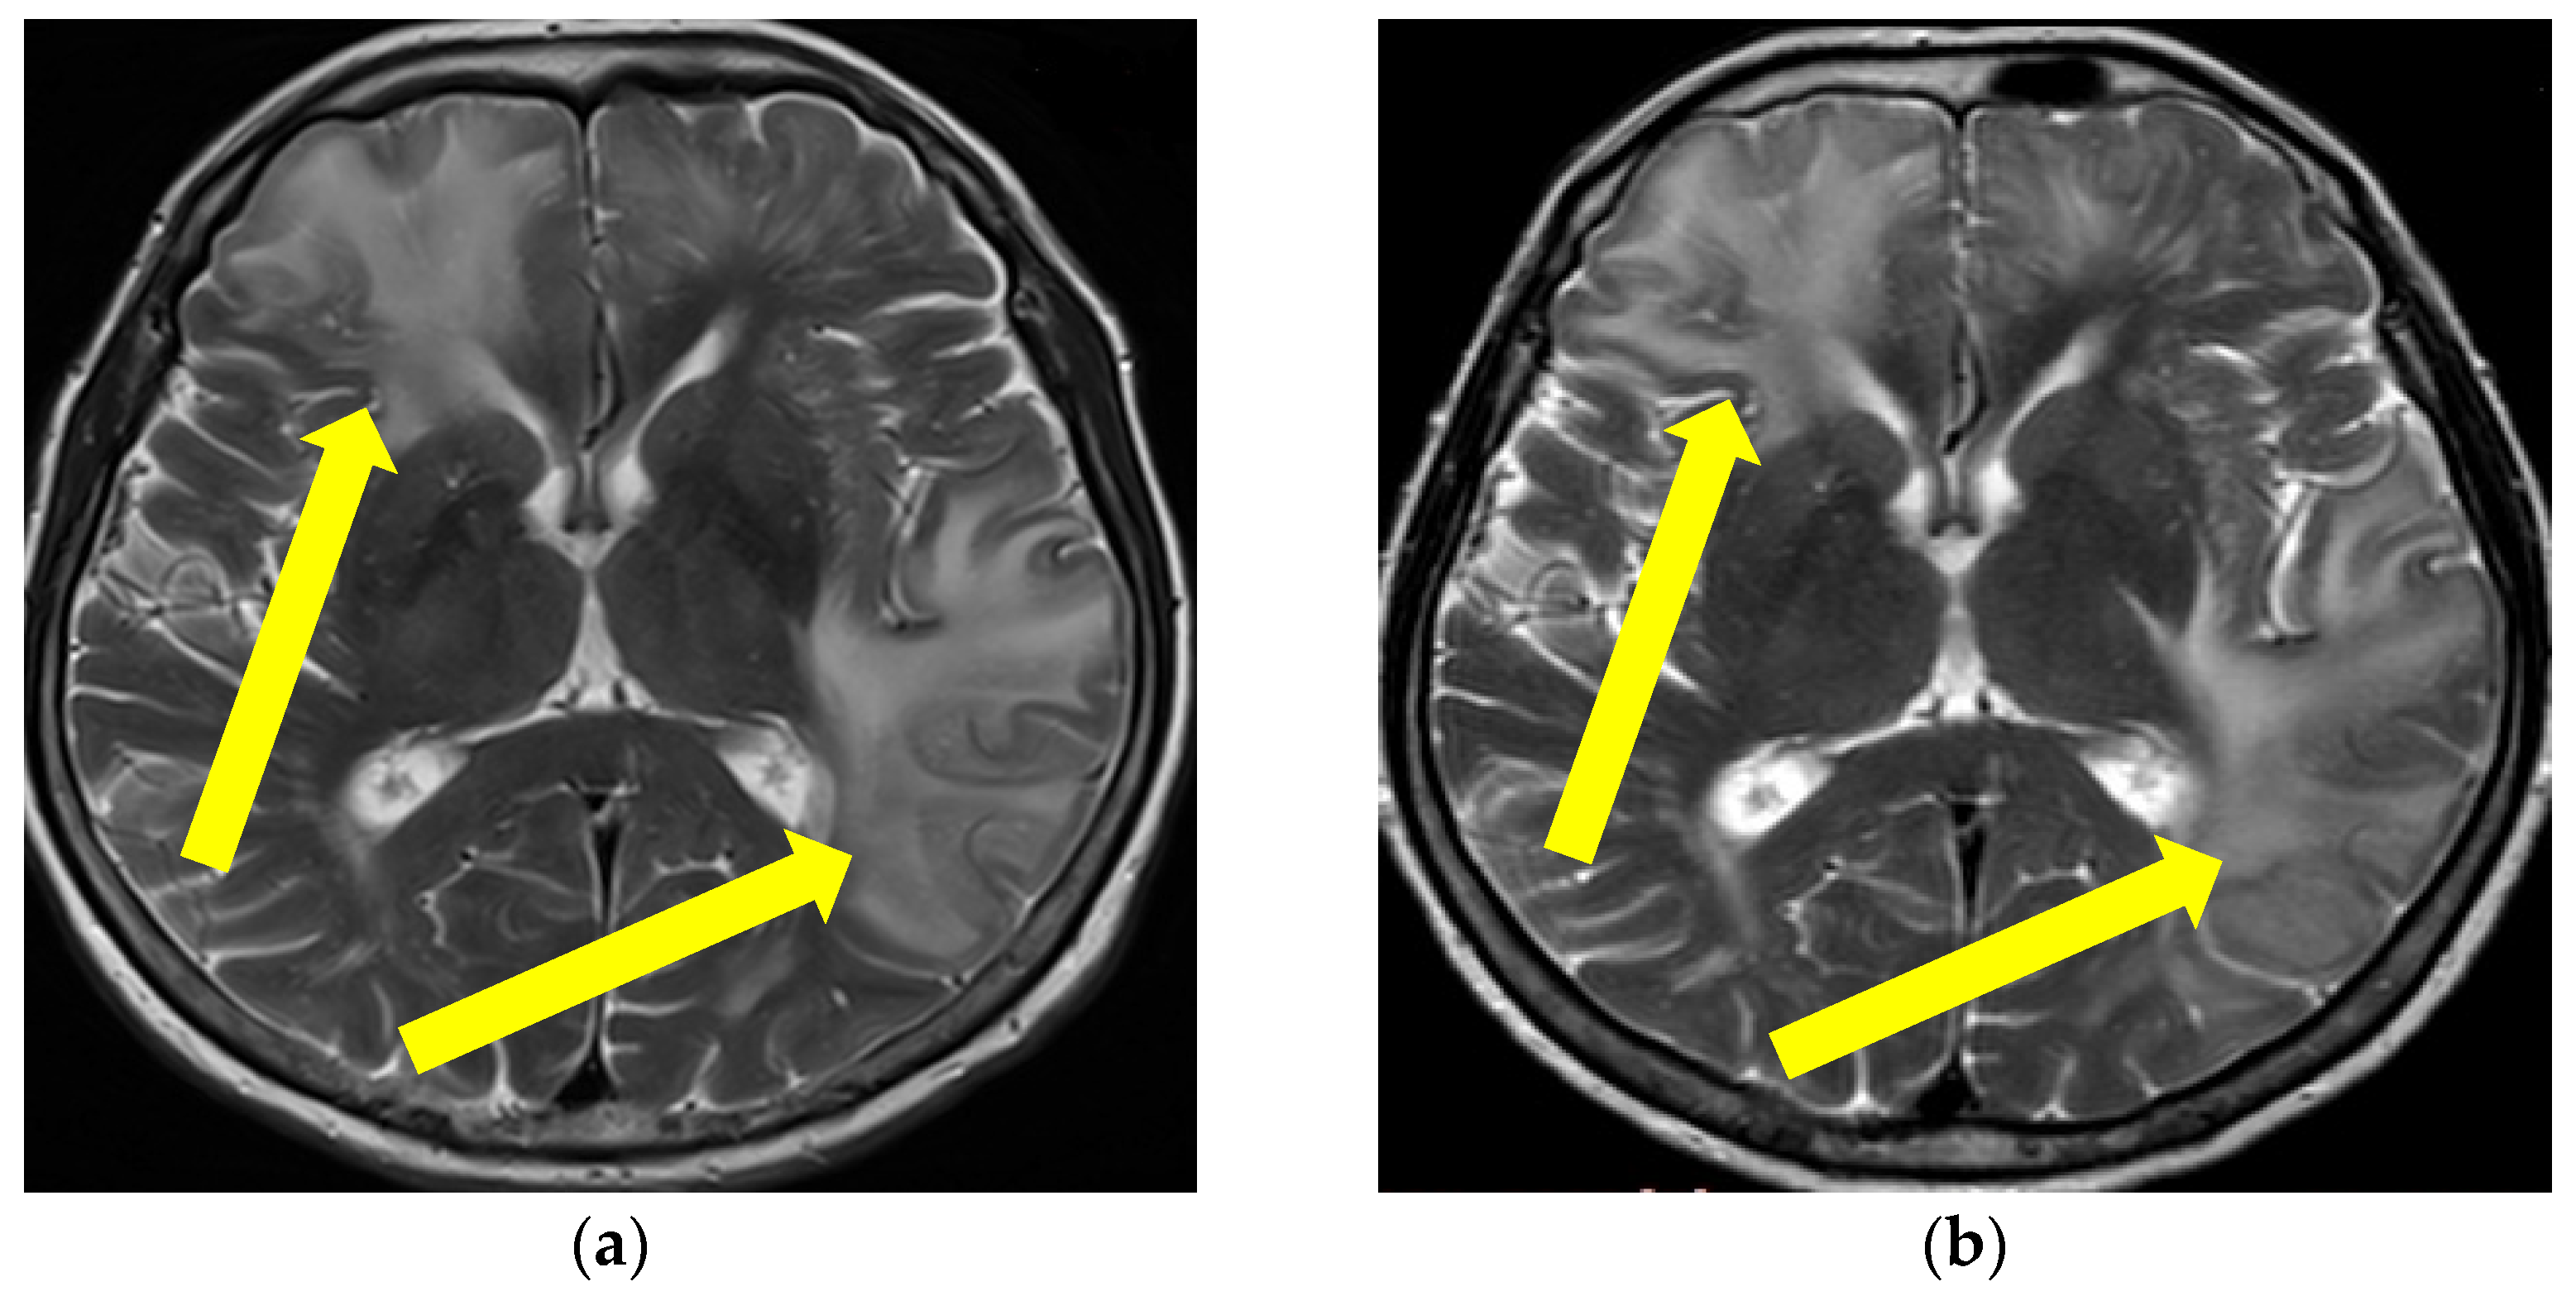

Figure 4.

Initial MR axial T2*W sequence (a) and control MRI one month after therapy initiation (b): (a) showing bilateral multiple punctiform hypointensities supratentorially, representing deposits of hemosiderin on the first MR examination, (b) showing the persistence of bilateral multiple punctiform hypointensities supratentorially. Yellow circles are showing the bilateral location of the multifocal hypointensities (Patient No. 2).

Based on these findings a diagnosis of probable CAA-rI was established. Initially, pulse methylprednisolone (1 g/daily) therapy was administered for 5 days, followed by oral prednisone (1 mg/kg), slowly tapered down during the next 3 months. During the immunosuppressive treatment, our patient had a verified septic state but was successfully treated with intravenous antibiotic therapy. The follow-up MR examination one month after treatment initiation showed mild progression of the WMH lesions with the persistence of previously noted microbleeds (Figure 3 and Figure 4). Although her neurological examination was without focal neurological deficit, the patients was still complaining about the presence of headaches and her control neuropsychological assessment was mildly improved from the initial mini-mental state examination (MMSE) 22/30 to MMSE 23/30. Thus, treatment with oral prednisone (10 mg/daily) was reintroduced. The third follow-up MR examination after six months showed resolutions of the WMH lesions (not shown), while her neuropsychological assessment was further improving.